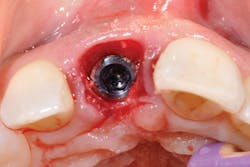

Figure 3: Tooth No. 8 shattered as expected during extraction.

Extractions are a horrifying concept, yet in actuality there is pressure but no pain. Tooth No. 8, as predicted, shattered with the first touch (see Figure 3). The sound was terrible, a super loud snap. It took a moment for me to regroup, take a breath, and literally grieve the loss of my front tooth. It sounds ridiculous, but for me this was my true moment of loss, and then beginning. The prosthodontist decided that we would prepare each tooth individually, from start to finish. One tooth out, lots of drilling to remove the root, then synthetic bone-graft material mixed with my own bone (see Figure 4). As it happens, I was offered bovine bone, treated cow bone. As a nonmeat eater, there was not a chance I could handle that in addition to losing my two front teeth! Choosing synthetic was a personal option for me. Let your patients know there are cow, pig, cadaver, and synthetic materials available; it is a personal choice (see Figure 5).